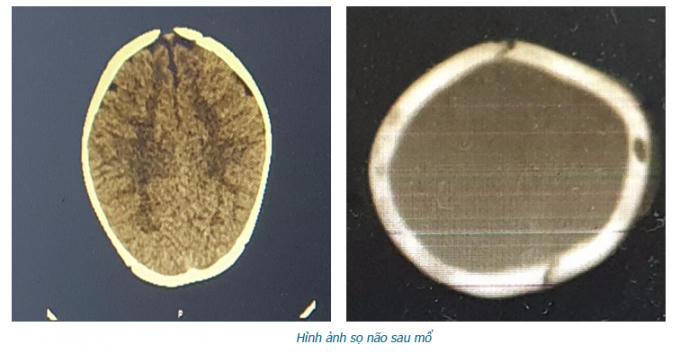

Thông tin từ Khoa Ngoại Thần kinh, Bệnh viện đa khoa tỉnh Phú Thọ, mới đây, các bác sĩ của khoa đãtiếp nhận và tiến hành phẫu thuật để nâng xương lún cho bệnh nhi 8 tháng tuổi bị ngã lún sọ thái dương đỉnh trái.

Tại đây, bé L đã được làm các cận lâm sàng và được chẩn đoán lún sọ thái dương đỉnh trái, vết lún sâu 1cm.

BSCKII, Hà Xuân Tài, Phó Khoa Ngoại Thần kinh, Bệnh viện Đa khoa tỉnh Phú Thọ, trực tiếp phẫu thuật cho bệnh nhi L cho biết: “Lún sọ pingpong thường gặp ở trẻ nhũ nhi dưới 1 tuổi. Nguyên nhân thường do tai biến sinh có thủ thuật, hay trẻ bị ngã khi tập đứng, tập đi và trẻ bị ngã ở độ cao thấp. Vị trí thường gặp hộp sọ là vùng đỉnh. Do ở trẻ nhũ nhi hộp sọ có khả năng tự điều chỉnh tốt nên hiếm khi phải mổ cấp cứu ngay, trừ những trường hợp lún sọ mức độ nhiều, tổn thương rách màng cứng và tổn thương não. Tuy nhiên cha mẹ thường rất lo lắng và yêu cầu được mổ ngay vì liên quan đến thẩm mỹ hộp sọ và sợ ảnh hưởng đến thần kinh của trẻ về sau”.

Đến chiều ngày 12/9, sức khỏe của bệnh nhi đã ổn định trở lại và được xuất viện.